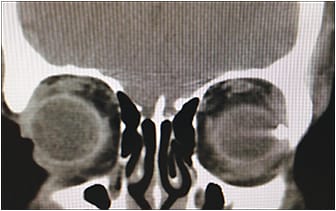

Imaging is a very important part of the workup of a patient with an OGI. Computed tomography (CT) scans are fast, widely available, and effective at detecting a wide range of foreign bodies.6 Thin (1-mm) cuts with coronal (Figure 5), axial (Figure 6), and sagittal views are ideal to identify IOFBs and to assess the globe contour, site of posterior rupture, and any other cranial (eg, subarachnoid hemorrhage) or ophthalmic traumatic sequelae (eg, orbital fractures or retrobulbar hemorrhage). Although CT is able to detect most IOFBs well, wood IOFBs are usually hypodense and may be mistaken for air or fat.7 The presence of linear-appearing air should raise suspicion for a wood IOFB. Measuring the Hounsfield units of an IOFB identified on CT may provide some insight into its composition.6